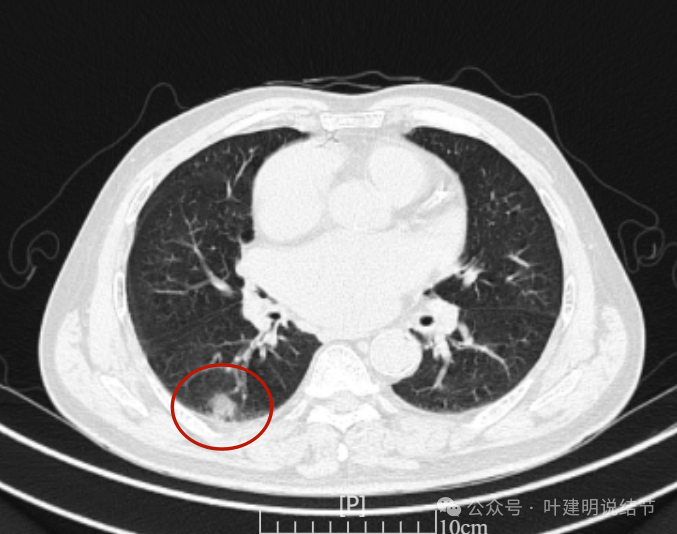

这是冠状位、矢状位与轴位的影像。

增强纵隔窗见病灶内部的密度好像低于周围区域,像坏死。

邻近胸膜无牵拉,灶内有低密度区,局部有点状液性密度。邻近胸膜较为广泛的增厚或胸膜反应。

病灶与胸膜接触面宽,病灶内部密度较低。